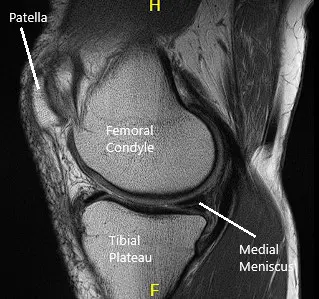

MRI of the left knee suggested tear of the posterior horn and posterior horn/body segment junction medial meniscus, with mild meniscal extrusion into the medial gutter and mild chondromalacia patella.

MRI of the knee in sagittal and coronal sections